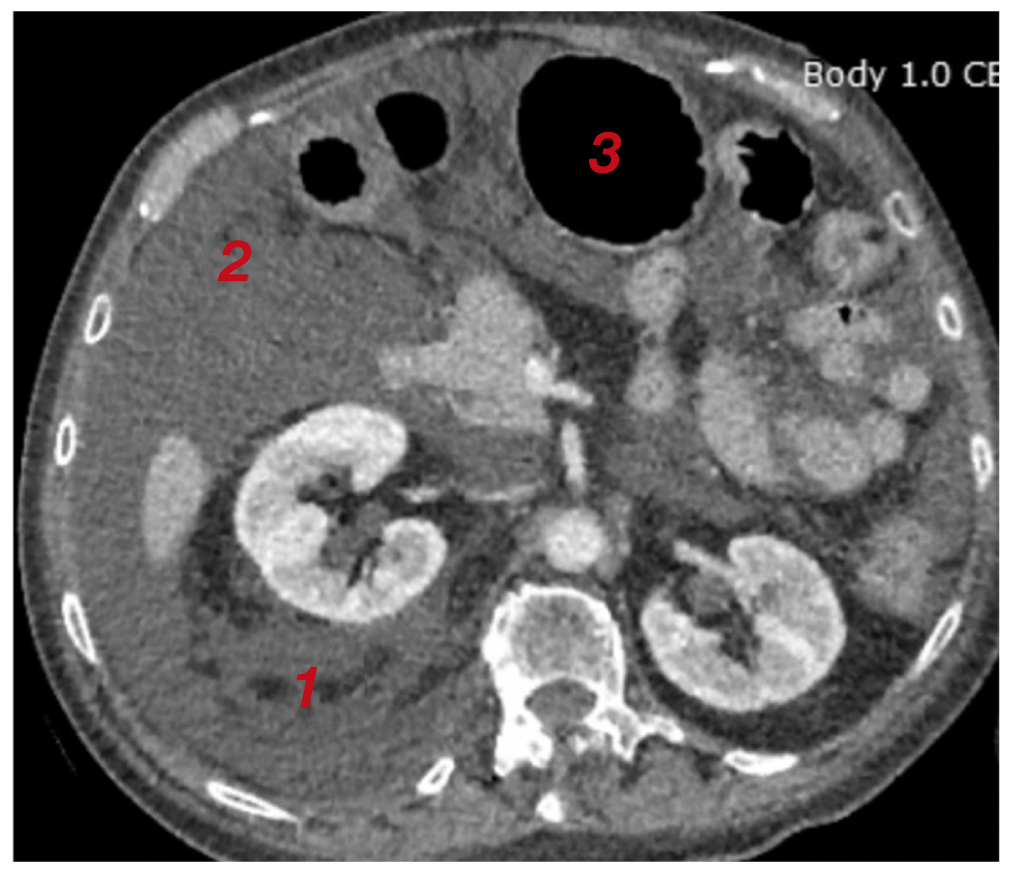

По завершении операции выполнен поворот пациентки на спину, отмечены значимое увеличение живота в объёме, тимпанический звук при перкуссии. После восстановления уровня сознания пациентка была экстубирована; предъявила жалобы на тянущие боли в области живота, позывы к мочеиспусканию, затруднение дыхания, в связи с чем направлена в отделение реанимации и интенсивной терапии (ОРИТ) для послеоперационного наблюдения и дообследования. По данным УЗИ органов брюшной полости выявлено наличие свободной жидкости. Компьютерная томография (КТ) органов брюшной полости показала наличие свободной жидкости в брюшной полости, отёк забрюшинного пространства и паранефральной клетчатки справа (рис. 4–6).

Рис. 6. Отёк забрюшинного пространства и паранефральной клетчатки справа (1); свободная жидкость в брюшной полости (2); желудок, раздутый газом (3), по данным компьютерной томографии.

Fig. 6. Edema of the retroperitoneal space right paranephral adipose tissue (1); free liquid in the abdominal cavity (2); the stomach, filled with gas (3), according to computed tomography.